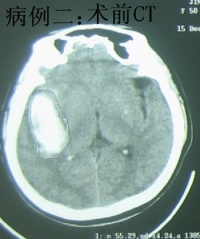

根据高血压病史及临床特点,一般不难作出临床诊断。脑CT、磁共振扫描对诊断最有帮助,不仅可以早期确诊,而且能够精确了解出血的部位、出血量、波及范围、有无脑室穿破以及血肿周围脑组织情况。发病年龄多在中年以上,既往有高血压病史,寒冷季节发病较多。常突然发病,出现剧烈头痛、呕吐、偏瘫及意识障碍,即应考虑脑出血。作一次CT 检查仅需几分钟即可完成,这是高血压脑出血诊断上的重大进展。新近使用的磁共振检查也能帮助脑出血在短时间内作出准确的诊断。